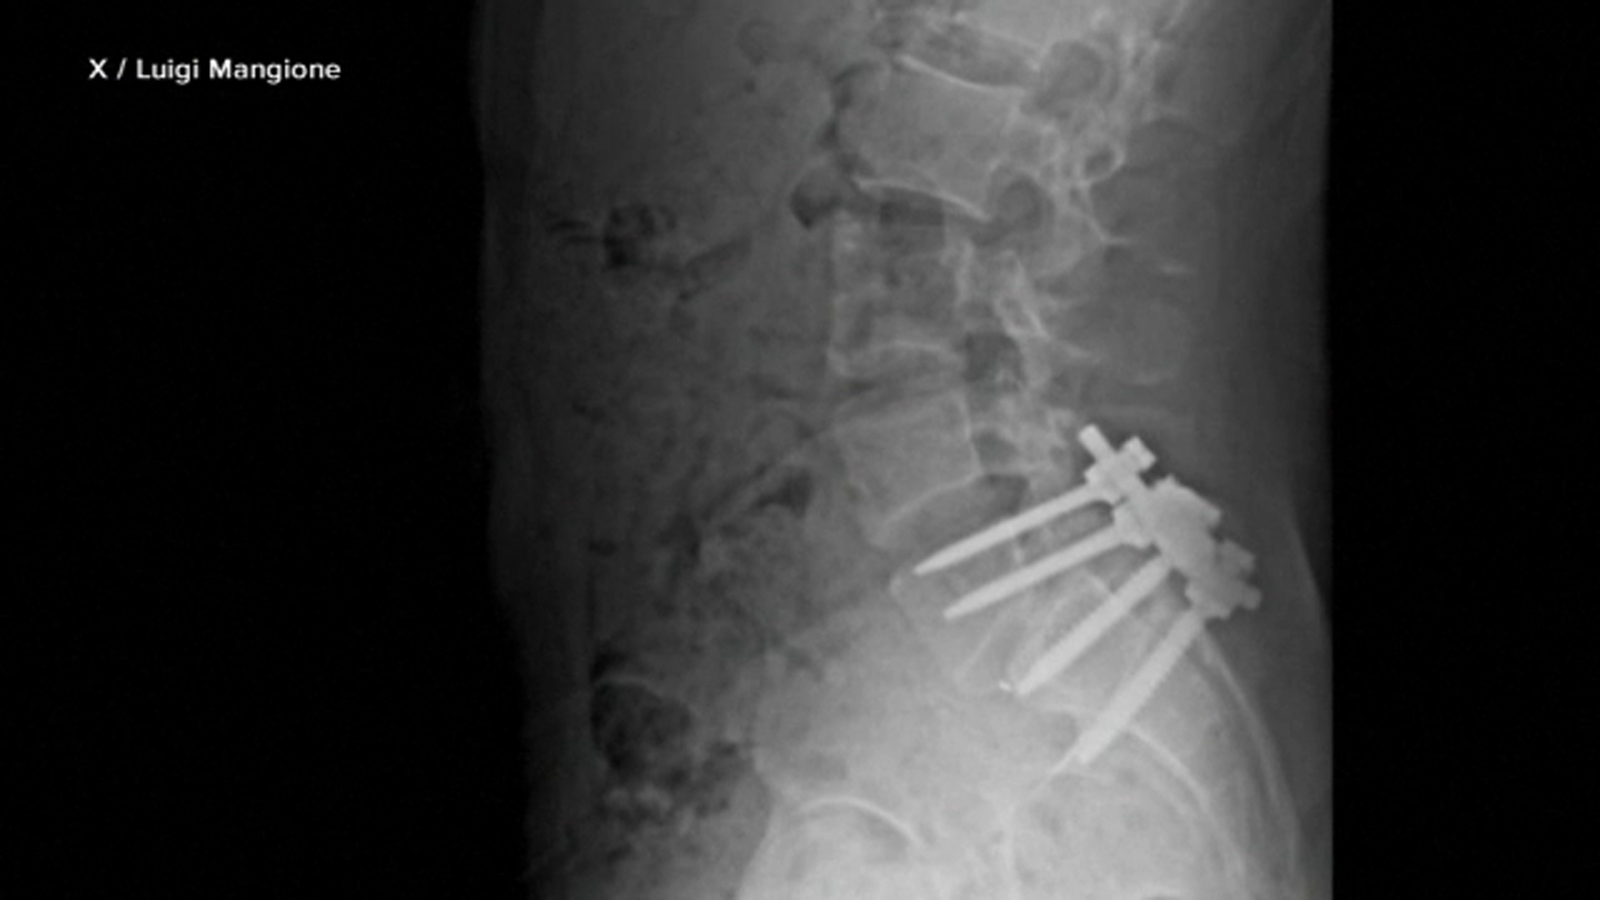

On an X profile, believed to be operated by Mangione, the cover image shows an image of an X-ray depicting pins from a spinal fusion surgery.